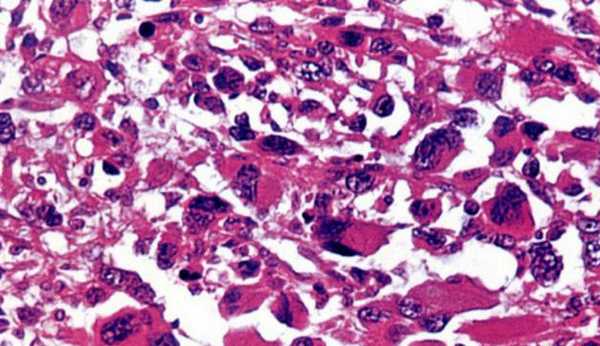

Рабдомиосаркомы встречаются крайне редко у взрослых и представляют собой скопление слабо дифференцированных продолговатых или округлых клеток, страной формы и имеющих большие ярко окрашенные ядра. В середине опухоли могут находиться сероватые участки некроза и кровоизлияния. В патогенез может быть вовлечена не только мышечная ткань, но и подкожно-жировая клетчатка, и кожа, и слизистые.

Микроскопический препарат рабдомисаркомы

Рабдомиосаркома обычно происходит из рабдомиобластов - предшественников скелетных мышц и поражает глубокие слои мягких тканей или поверхности слизистой оболочки, кожных покровов, представляя собой объемное образование в определенной области тела, где есть поперечно-полосатая мускулатура либо её мезенхимальные предшественники. При этом разрастание происходит полиморфно и клетки утрачивают сходство с поперечно-полосатой мускулатурой, хотя и могут иметь некую поперечную исчерченность.